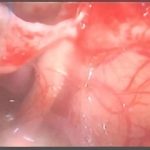

手術前2

摘出 中

摘出 後